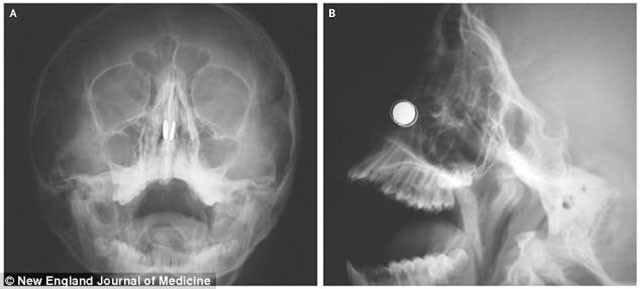

Röntgen filmlerine bakan doktorlar burun direğinin yanlarında birbiriyle aynı hizada diske benzer iki yabancı madde buldu.

Mıknatıslar durdukça kıkırdağı aşındırmaya başlamıştı.